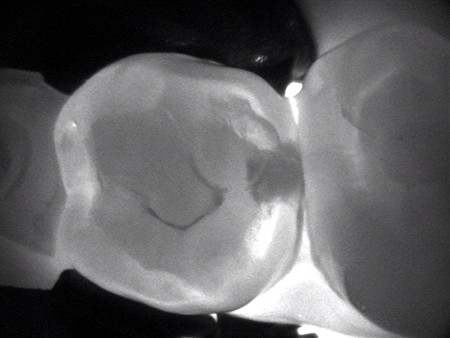

CariVu

Dexis Dental has a new version of a handheld and portable transillumination device, CariVu. It uses patented technology to support the identification of occlusal, interproximal, and recurrent caries and cracks. The device is designed to engulf a tooth in their patented near infrared light. The tooth appears transparent. Carious lesions absorb light and try to mimic what interproximal decay looks like on a radiograph. Dexis believes they have an edge over devices that fluoresce in that the teeth do not need to be clean of bacteria, the device does not require calibration before each use, and the device reports more of the physical condition of a tooth.